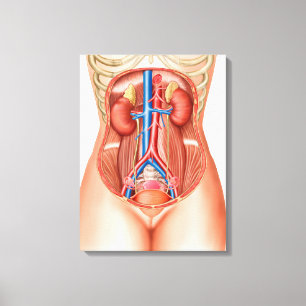

Anatomi hos kvinnlig kropp med reproduktionsorgan hälsningskort

Försäljningspris 49,00 kr. Ursprungligt pris 54,00 kr.